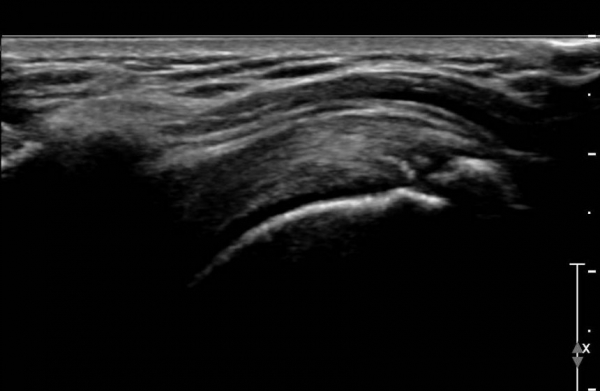

ÃÊÀ½ÆÄ °Ë»ç :  ¿À±¸µ¹±â °ßºÀÀδë Á¾´Ü¸é°Ë»ç¿¡¼­ ÀÎ´ë ½ÉÃþ¿¡ ¼ö¾×Àú·ù°¡ °üÂûµÇ´Âµ¥(»çÁø 1) ÀÌ °ÍÀº

¸¸¼ºÀûÀÎ Ãæµ¹ÁõÈıºÀ» ¾Ï½ÃÇÑ´Ù.